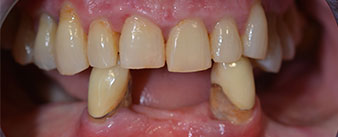

La paciente de 64 años se presentó con una dentición residual compuesta por las piezas dentales 38, 33 y 43 en el maxilar inferior y con una prótesis temporal fijada con ganchos en el maxilar inferior (figs. 1 y 2).